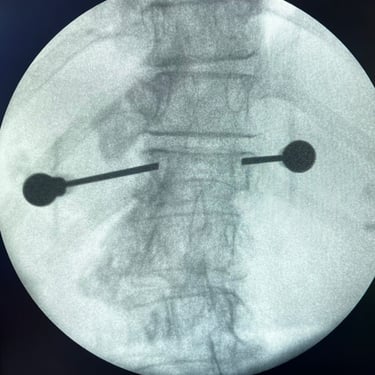

🧠 Fractura vertebral lumbar – Artrodesis con tornillos transpediculares (FTP).

La fractura vertebral lumbar puede causar inestabilidad y dolor severo. La artrodesis con tornillos transpediculares es una técnica quirúrgica eficaz que estabiliza la columna, protege las raíces nerviosas y mejora la recuperación funcional del paciente.